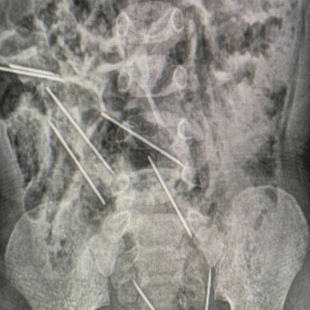

Διεθνή Περού: Αγόρι κατάπιε οκτώ μεγάλες βελόνες από ενέσεις για ζώα «Ίσως τις κατάπιε όταν έπαιζε εκεί» LIFO NEWSROOM

14.9.2023 Διεθνή Περού: Αγόρι κατάπιε οκτώ μεγάλες βελόνες από ενέσεις για ζώα LifO Newsroom 14.9.2023 «Ίσως τις κατάπιε όταν έπαιζε εκεί» LIFO NEWSROOM